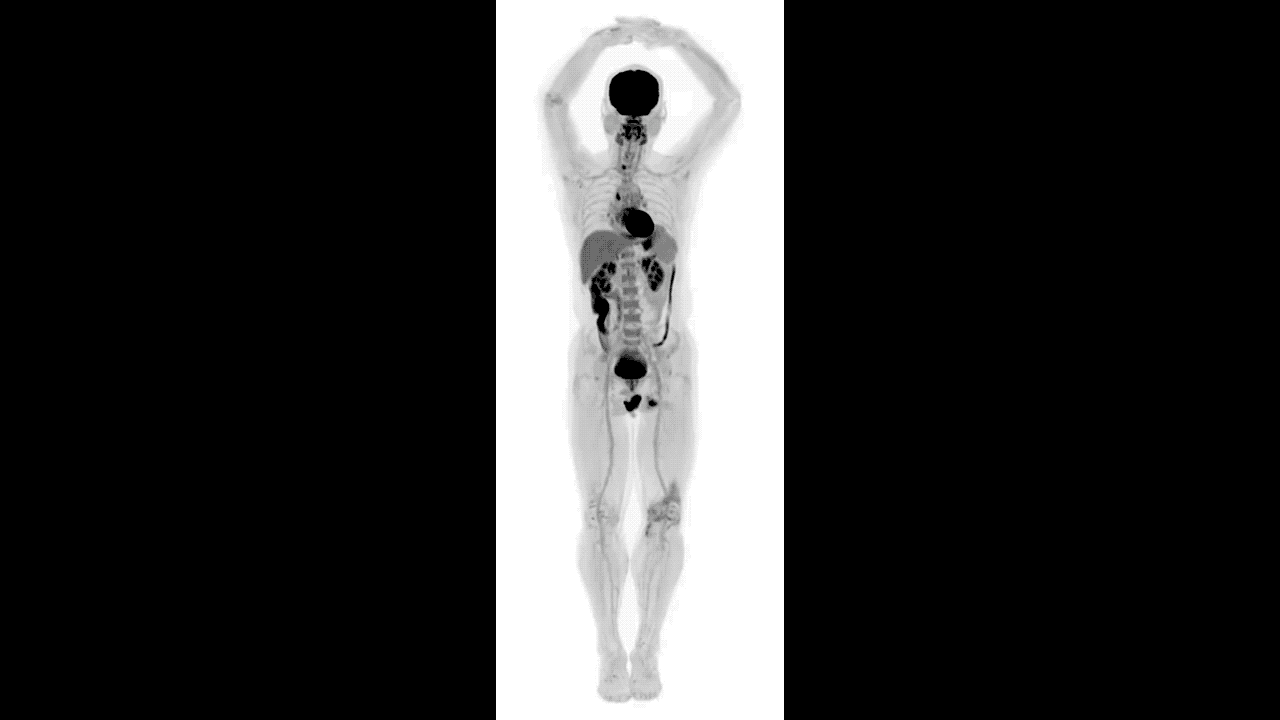

An unbelievably clear look at what goes on inside our bodies.